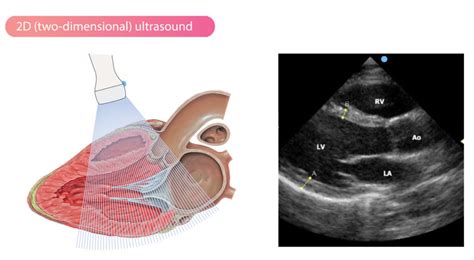

Echocardiography is a non-invasive medical examination that employs sound waves to generate visual representations of the heart. This widely-used diagnostic tool in cardiology allows doctors to assess the heart's structure and performance. It offers insights into the heart's pumping capacity, identifies any irregularities in the heart valves or chambers, and detects potential signs of heart disease or damage.

During an echocardiogram, a handheld device referred to as a transducer captures the sound waves that bounce back from the heart. Subsequently, these sound waves are converted into images of the heart that can be observed on a computer screen. The procedure is painless and typically lasts between 30 to 60 minutes. Importantly, it is also a safe examination without any exposure to harmful radiation.